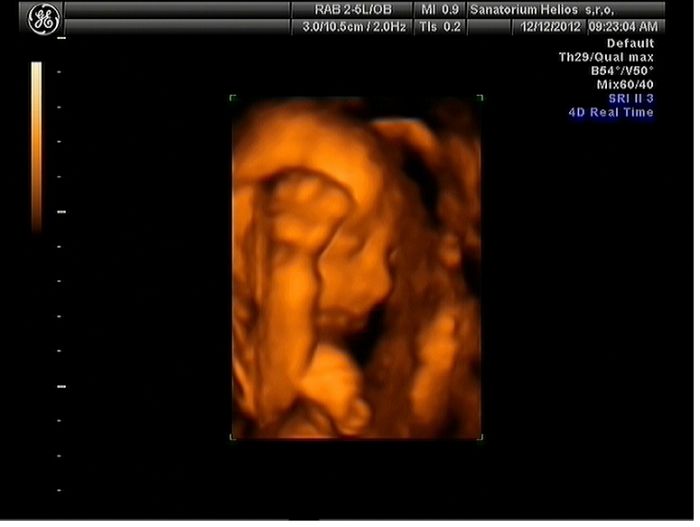

Holky moje to byla pecka

dojdu tam, vysolim love, cekam.. pani doktorka vse nachystala a zacli jsme .. mladej byl zvhuru a mlel se jak blazen a porad rucicky pred oblicejem, ma je tak fakt porad hahaha prej oblibena poloha, kdyz uz tam nemel ruce, tak tam byla placenta takze mlha, nebo pres hlavu mu sel pupecnik haha a kdyz uz holky vypadalo ze fotime, tak zacal strkat pred oblicek nohy

stouchali jsme do nej, ja se prekulovala z bolku na bok

mame par fotek, ale lepsi proste nesli.. video mame i s merenim a srdecnim tepem.. tak Eldinek ma neco malinko pres 500g ..

posilam fota.. jako lepsi proste nebyly hahahah